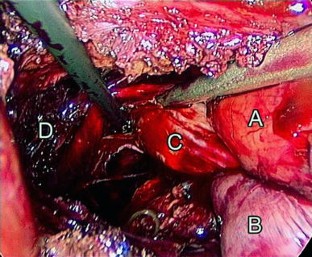

Fig. 2